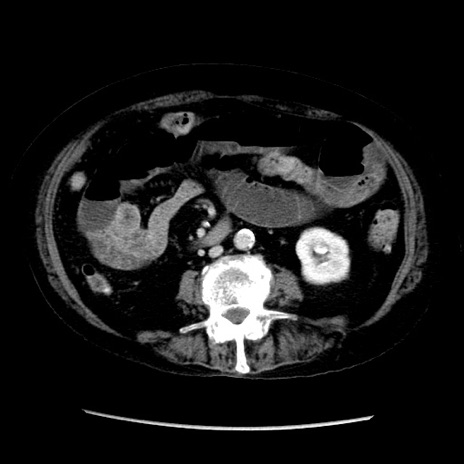

症例14(横断像)

【症例】 90歳代女性

【主訴】 腹痛・嘔吐

【現病歴】今朝から左側腹部痛を認めた。 経過観察していたが、嘔吐を認めたため来院。

【既往歴】 子宮癌術後

【身体所見】 意識清明、BP 127/54mmHg、P 98bpm Sp02 95%(RA)、BT 35.8°C、腹部平坦・軟腸ぜん動音聴取良好、右下腹部圧痛(+) 反跳痛なし

【データ】WBC 9800、CRP 0.46